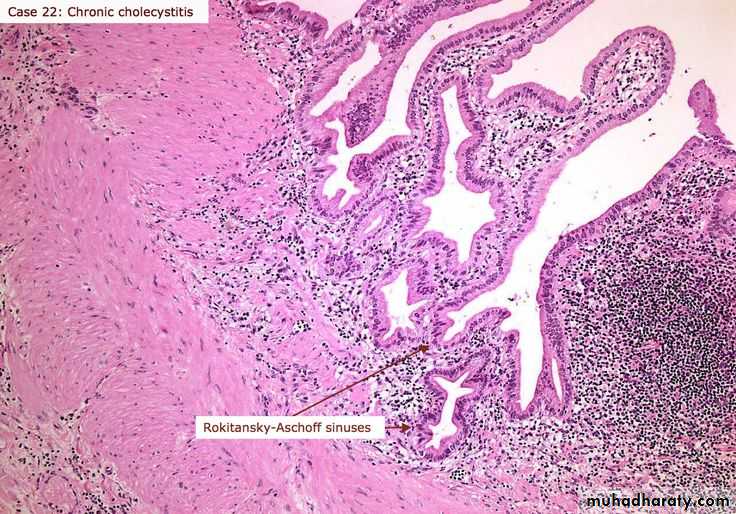

Differences between

Acute Inflammation